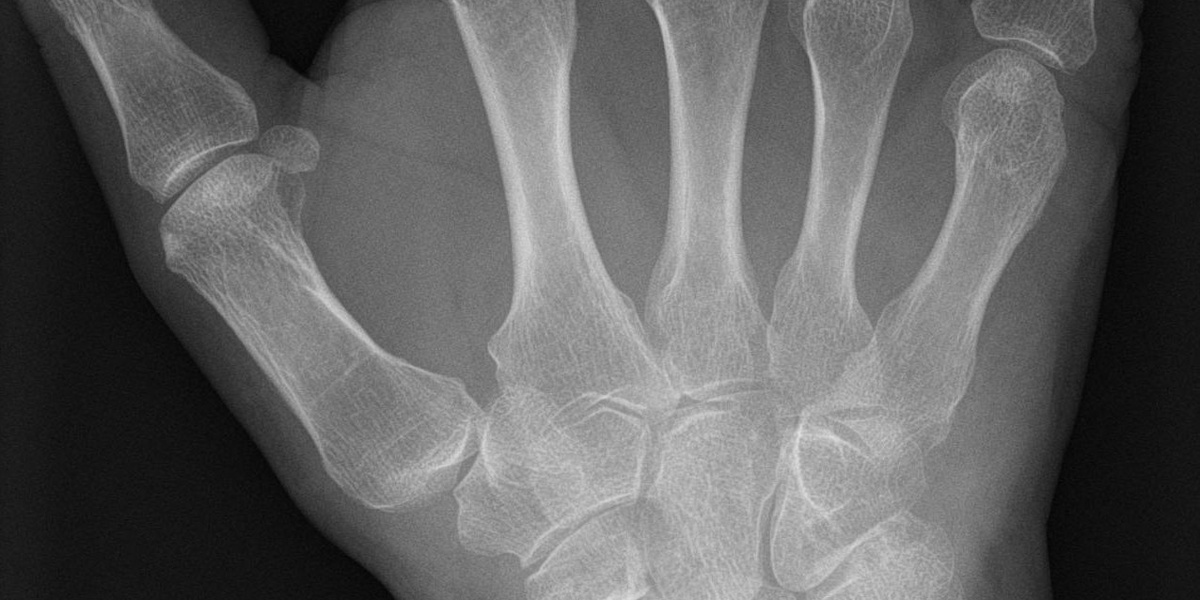

Scaphoid

Scaphoid sits on the thumb side of the wrist and helps bridge proximal and distal carpal rows. It transmits load from hand to forearm, develops from a single ossification center, and is prone to non-union due to tenuous blood supply.